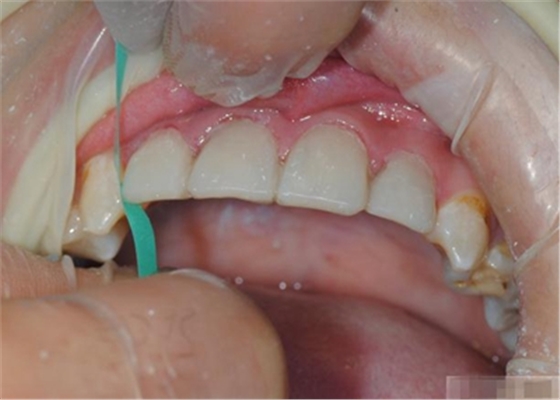

制作舌側(cè)背板

使用事先制作完成的硅橡膠模板。它是由技師在做好的美學(xué)蠟型的模型上制作的。這樣的方法為牙醫(yī)提供了許多便利:

制作 背板

修復(fù)鄰壁